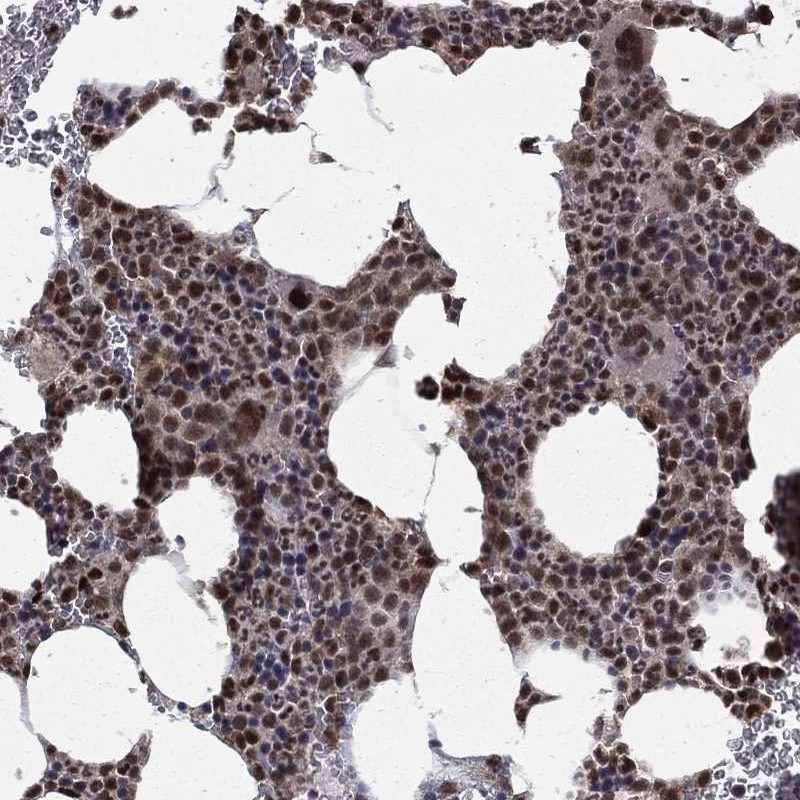

Immunohistochemical staining of human bone marrow shows strong nuclear positivity in hematopoietic cells.